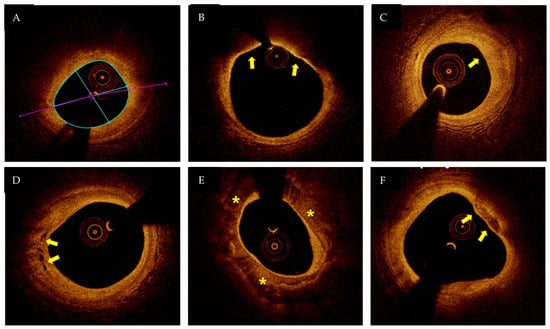

2. Role of OCT

- Jia, H.; Abtahian, F.; Aguirre, A.D.; Lee, S.; Chia, S.; Lowe, H.; Kato, K.; Yonetsu, T.; Vergallo, R.; Hu, S.; et al. In Vivo Diagnosis of Plaque Erosion and Calcified Nodule in Patients with Acute Coronary Syndrome by Intravascular Optical Coherence Tomography. J. Am. Coll. Cardiol. 2013, 62, 1748–1758. [Google Scholar] [CrossRef] [PubMed]

- Usui, E.; Matsumura, M.; Smilowitz, N.R.; Mintz, G.S.; Saw, J.; Kwong, R.Y.; Hada, M.; Mahmud, E.; Giesler, C.; Shah, B.; et al. Coronary morphological features in women with non-ST-segment elevation MINOCA and MI-CAD as assessed by optical coherence tomography. Eur. Hearth J. Open 2022, 2, oeac058. [Google Scholar] [CrossRef]

- Mas-Lladó, C.; Maristany, J.; Gómez-Lara, J.; Pascual, M.; Alameda, M.D.M.; Gómez-Jaume, A.; Peral-Disdier, V. Optical Coherence Tomography for the Diagnosis of Exercise-Related Acute Cardiovascular Events and Inconclusive Coronary Angiography. J. Interv. Cardiol. 2020, 2020, 1–10. [Google Scholar] [CrossRef] [PubMed]

- Zeng, M.; Zhao, C.; Bao, X.; Liu, M.; He, L.; Xu, Y.; Meng, W.; Qin, Y.; Weng, Z.; Yi, B.; et al. Clinical Characteristics and Prognosis of MINOCA Caused by Atherosclerotic and Nonatherosclerotic Mechanisms Assessed by OCT. JACC Cardiovasc. Imaging 2022, in press. [Google Scholar] [CrossRef] [PubMed]

- Nishiguchi, T.; Tanaka, A.; Ozaki, Y.; Taruya, A.; Fukuda, S.; Taguchi, H.; Iwaguro, T.; Ueno, S.; Okumoto, Y.; Akasaka, T. Prevalnence of spontaneous coronary artery dissection in patiens with acute coronary syndrome. Eur. Heart J. Acute Cardiovasc. Care 2016, 5, 263–270. [Google Scholar] [CrossRef]

- Barbieri, L.; D’Errico, A.; Avallone, C.; Gentile, D.; Provenzale, G.; Guagliumi, G.; Tumminello, G.; Carugo, S. Optical Coherence Tomography and Coronary Dissection: Precious Tool or Useless Surplus? Frontiers 2021, 59, 1073–1079. [Google Scholar] [CrossRef]

- Gerbaud, E.; Arabucki, F.; Nivet, H.; Barbey, C.; Cetran, L.; Chassaing, S.; Chassaing, B.; Lesimple, A.; Cochet, H.; Montaudon, M.; et al. OCT and CMR for thediagnosis of patients presenting with MINOCA and suspected epicardial causes. JACC Cardiovasc. Imaging 2020, 13, 2619–2631. [Google Scholar] [CrossRef] [PubMed]

- Reynolds, H.R.; Maehara, A.; Kwong, R.Y.; Sedlak, T.; Saw, J.; Smilowitz, N.R.; Mahmud, E.; Wei, J.; Marzo, K.; Matsumura, M.; et al. Coronary Optical Coherence Tomography and Cardiac Magnetic Resonance Imaging to Determine Underlying Causes of MINOCA in Women. Circulation 2011, 124, 1414–1425. [Google Scholar] [CrossRef] [PubMed]